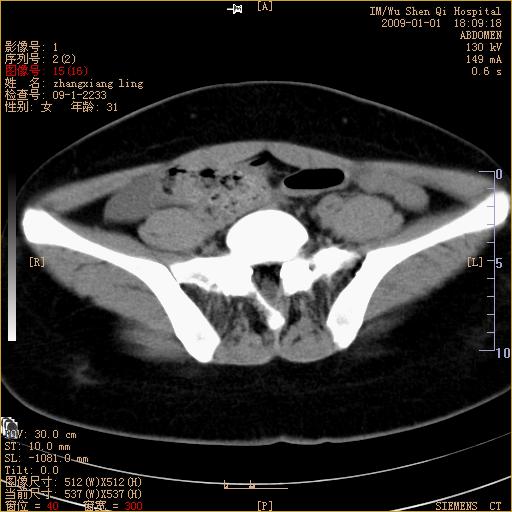

标题: CT17527:F31Y,腹痛伴血便9小时 [打印本页]

标题: CT17527:F31Y,腹痛伴血便9小时

升结肠肠壁不规则增厚,肠腔狭窄,考虑升结肠占位,建议增强扫描

升结肠肠壁不规则增厚,肠腔狭窄,考虑升结肠占位,建议增强扫描,不除外肠套叠.

升结肠肠壁不规则增厚,似呈同心圆改变,其有积液。结合病史首先考虑肠套叠伴肠壁坏死可能性大,结肠肿瘤待排。

患者已手术,结果肠系膜血栓形成肠坏死

结果:患者已手术,结果肠系膜血栓形成肠坏死。回过头再看局部肠壁增厚有分层(高密度坏死及低密度水肿)表现。